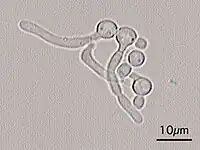

Ce n'est que par la suite que se développe l’hypothèse spécifique de la plaque, suivie par un changement de paradigme qui conduit à l’hypothèse écologique de la plaque[26]. En raison de nombreux facteurs pathogènes, l'émail de la dent est détruit en plusieurs étapes : une disponibilité continue de glucides fermentescibles, qui conduisent à une valeur du pH continument abaissée est la force motrice de la destruction d'une homéostasie de la plaque dentaire. Cette pression écologique stimule la multiplication de germes, les uns produisant de l'acide et d'autres tolérants aux acides, comme le streptococcus mutans et les lactobacilles. Il y a de plus une interaction entre le streptococcus mutans et la levure candida albicans, par laquelle la bactérie change de virulence. La levure produit des molécules signaux, qui suscitent la production par les gènes de la bactérie d'antibiotiques propres à la cellule. La bactérie peut, par la levure, acquérir des gènes étrangers[27].

Bien que dans les temps modernes, le « ver de la dent » macroscopique soit ridiculisé, les bactéries et levures apparaissent, au microscope, semblables à des vers[réf. souhaitée].